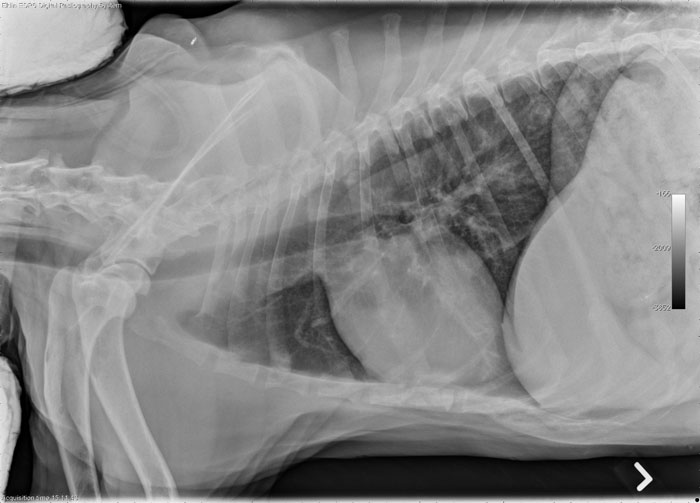

X-rays are used in a variety of cases. They are vital in detecting bone fractures, bladder stones, and for finding and assessing tumors. They can be helpful in locating foreign material such as swallowed fishhooks and safety pins. They are used to aid in decision making regarding Cesarean Section surgery by allowing the surgeon to actually see the size and number of fetuses present.

In order to have a quality x-ray film the subject must be motionless for the fraction of a second the exposure it occurring. Some cats and dogs are very cooperative and others will need sedation to calm them for the procedure. And other special situations require that the dog or cat be completely relaxed for a particular view or procedure…and that means a light anesthetic is required. Here in the x-ray room we will show you some interesting x-rays and brief descriptions of patients who benefited from the use of the x-ray machine. And the things that dogs and cats eat!!! We will show you some of the rocks, nails, bones, and toys that end up in the stomachs of our pets.